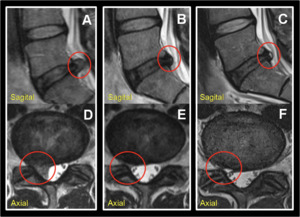

The knowledge of all these processes has led to a deep research on the response of different therapeutic agents to slow down the natural evolution of disc degeneration.3 Prominent among these is PRGF infiltration,^3, 4^ that our group has been performing for 10 years through minimally invasive techniques, both in lumbar and cervical spine.

Starting from an action protocol with strict inclusion and exclusion criteria, more than 1300 protocols have been carried out which have been evaluated through pre and 6/12/24-months post MRI (Fig.1), Numerical Rating Scale (NRS) and quality of life and pain questionnaires such as Spine COMI and OSWESTRY. We highlight the improvement of neuritic pain (Fig.2) and pain caused by mechanical overload in the FVU, and the permanent improvement in the degenerative process of the disc and endplate.5